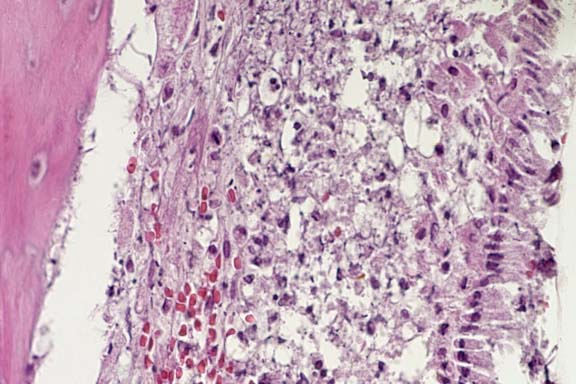

Case 24-1. Nasal cavity. A layer of necrotic inflammatory debris and focal hemorrhage is expanding the lamina propria, over the bone (left). 40x

AFIP Diagnoses: 1. Nasal cavity: Rhinitis, osteomyelitis, periodontitis, pulpitis, myositis, cellulitis, and vasculitis, necrotizing, neutrophilic and histiocytic, multifocal, moderate, with thrombosis, Syrian hamster (Mesocricetus auratus), rodent. 2. Vomeronasal organ: Degeneration and necrosis, multifocal, moderate.

Conference Note: In most sections viewed in conference, the nasolacrimal duct was partially or completely occluded by mucinous material with few inflammatory cells and sloughed epithelium. Degeneration of neurons in the vomeronasal organ is believed to be secondary to inflammation and necrosis of the more rostral portion of the nerve cell processes.